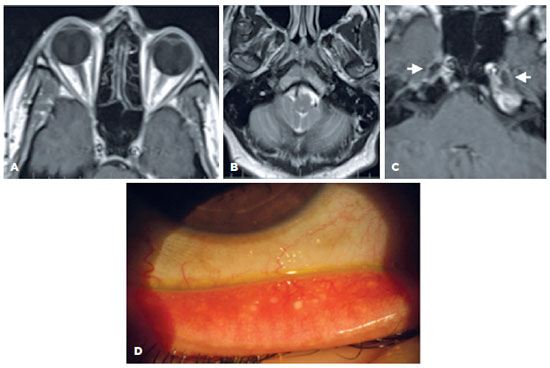

A 24-year-old white woman presented with DES over the last three years without dry mouth. She reported no comorbidities and no use of medications, except for treatment of acne with RA at 14 and 20 years of age, lasting for six months on both occasions. The ophthalmological examination demonstrated a visual acuity of 1.0 in both eyes (OU); a tear film break-up time (TFBUT) of 2 s in the right eye (OD) and 1 sin the left eye (OS); a grade 5 corneal fluorescein staining in OD and grade 3 in OS, with filamentary keratitis; and a Schirmer test (ST) showed absent tear flow (zero mm) in OU. Moderate MG dysfunction (MGD) with less than 30% of gland drop out, light expressibility, and cloudy oil secretion were observed. The ocular surface disease index (OSDI) was 70.45%, and the whole saliva flow was 0.13 ml/min (normal value, >0.1 ml/min). Serological tests for autoimmune and viral systemic diseases, including anti-Ro/SSA, anti-La/SSB, anti-dsDNA, anti-SM, anti-RNP, antinuclear antibody (ANA), and rheumatoid factor, were negative. A biopsy of her minor lip SG revealed a focus score of zero. MRI revealed the absence of the LG bilaterally (Figure 1A). The average normal LG volume is 0,580 cm3.

11-fig01tb.jpg)